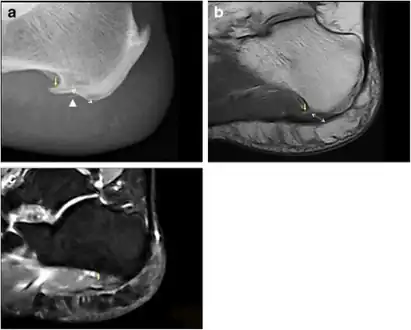

Spur outgrowths can be detected through physical exam followed by a lateral foot x-ray.

-

a) Plantar calcaneal spur at the origin of intrinsic muscles of the foot b) MRI confirms the presence of a calcaneal spur c) bone marrow oedema in the calcaneal spur -

Inferior calcaneal spur